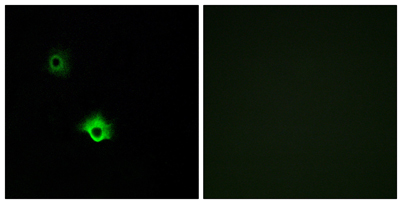

| Dilutions: | Western Blot: 1/500 - 1/2000. Immunofluorescence: 1/200 - 1/1000. ELISA: 1/40000. Not yet tested in other applications. |